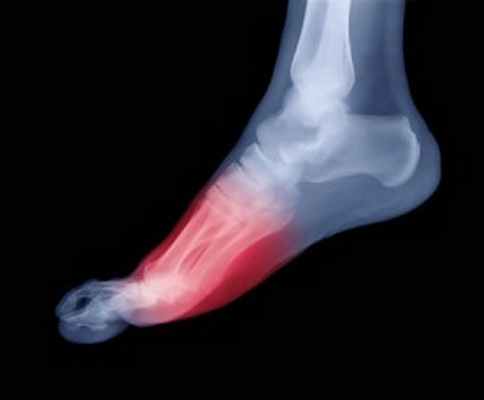

Переразгибание плюснефалангового сустава большого пальца ноги (в англоязычной литературе используется более короткий, но не имеющий аналогов на русском, термин «Turf Toe») представляет собой травму, обусловленную болезненным растяжением в области большого пальца ноги. Наиболее подвержены подобному повреждению спортсмены, выступающие на поверхностях с твердым покрытием (бетонном или деревянном, а также искусственном газоне), особенно игроки в американский футбол. У танцоров, футболистов, баскетболистов такая травма также не редкость. При постоянном травмировании, отсутствии полного заживления проблема приобретает хронический характер.

Растяжение связок большого пальца стопы — это перерастяжение или частичный разрыв сухожильно-связочного аппарата первого плюснефалангового сустава (сустав в основании пальца).

Растяжение связок происходит при чрезмерном тыльном или подошвенном (вниз или вверх) сгибании большого пальца. Чаще всего бывает у спортсменов, использующих слишком мягкую, не защищающую стопу обувь. Переразгибание большого пальца вызывает разрыв подошвенной капсулы плюснефалангового сустава. В редких случаях травма приводит к перелому или расхождению фрагментов сесамовидных костей (две небольшие косточки, расположенные с подошвенной стороны сустава).

Растяжение плюснефалангового сустава – это растяжение комплекса подошвенных связок большого пальца стопы. Боль возникает при активных и пассивных движениях отекшего сустава. Рентгенография нужна для исключения перелома. Лечение включает в себя фиксацию больного пальца вместе с соседним здоровым, анальгетики и, как правило, физиотерапию для профилактики хронической тугоподвижности сустава. Боль, которая сохраняется более нескольких недель, указывает на более тяжелое растяжение связок, которое может потребовать хирургического вмешательства.

Подошвенная сторона плюснефалангового сустава большого пальца ноги стабилизируется суставной капсулой, подошвенными мышцами и сухожилиями, а также комплексом сесамовидных костей.

Механизм возникновения растяжения связок на большом пальце ноги заключается в предельном тыльном сгибании плюснефалангового сустава большого пальца стопы (более чем на 90 ° ; например, при резком срывании с места, растяжение происходит в тот момент, когда пятка приподнята над землей). В англоязычной литературе такая травма называется "turf toe" (дословно с английского "газонный палец"), поскольку она была впервые описана у футболистов, играющих на искусственном газоне, который, являясь более твердой поверхностью, чем обычная трава, имеет более разрушающую силу при тыльном сгибании пальца при отталкивании и, таким образом, повышает риск гиперэкстензии и растяжения связок на большом пальце ноги. Тем не менее растяжение связок может возникать при занятиях любым видом спорта с бегом на короткие дистанции или прыжками, при котором возможна принудительная гиперэкстензия большого пальца ноги (например, бейсбол, футбол, гимнастика). Оно также может возникать приобрести хроническую форму при повторяющейся гиперэкстензии большого пальца ноги (например, при занятии танцами). Некоторые врачи спортивной медицины утверждают, что спортивная обувь, которая имеет жесткую и менее гибкую подошву, увеличивает риск растяжения связок большого пальца.

Наблюдается внезапная боль в плюснефаланговом (ПФ) суставе большого пальца стопы. Активные и пассивные движения сустава болезненны, сустав отечен.